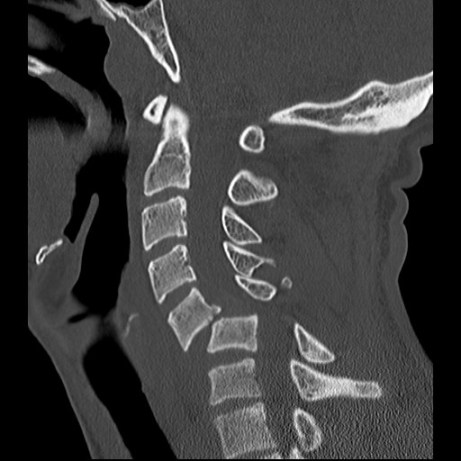

Not all spine injuries are dangerous, but Its impossible to know that without a hospital and xrays. Damien Martin below is one of the lucky ones.

There is no rule to this. You should always be suspicious. Your mate who’s been slammed on the sand with a broken collar bone/nose/wrist/concussion, or any distracting injury, is at high risk. Breaking your spine isn’t always as painful as you may expect. Another injury that IS painful can distract you from a spinal injury. Its well documented that 10 % of head injuries have a spinal injury aswel.

A missed spinal injury can have much more severe consequences than one that’s picked up and managed carefully. Paramedics are taught to assume that every trauma patient has a spinal injury.

The vast majority of spinal injuries are painful to some degree. Your mate rubbing their thumb down the boney points of your spine shouldn’t be painful, and if it is you should suspect a spinal injury. Obviously finding a step or lump in the spine is a clear indication that things aren’t as they should be!